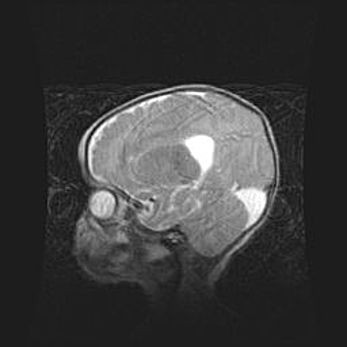

Мальформация Денди-Уокера. Киста задней черепной ямки.

Агенезия мозолистого тела.

Возраст: 2,5 месяца

Вес: 2420 г

Пол: женский

Окружность головы: 37 см

Срок гестации: 32 недели

Мальформация Денди—Уокера — редкий вид патологии ЦНС, представляющий собой врожденный порок развития каудального отдела ствола и червя мозжечка, ведущий к неполному раскрытию срединной (Мажанди) и латеральных (Лушка) апертур IV желудочка мозга. Для этогно синдрома характерна триада симптомов: гипотрофия червя мозжечка и/или полушарий мозжечка, кисты задней черепной ямки, гидроцефалия различной степени. В 70% случаев порок сочетается и с другими аномалиями головного мозга, в частности с агенезией мозолистого тела.